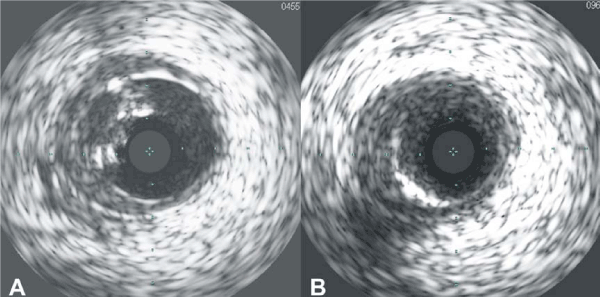

| Figure 3: A - Intravascular ultrasound (IVUS) of the RCA following initial stent implantation. The under-deployed struts of the stent and heavy calcium burden are visible. B - IVUS appearance following stentablation. The calcium burden and under- deployed stent struts are no longer visible. |